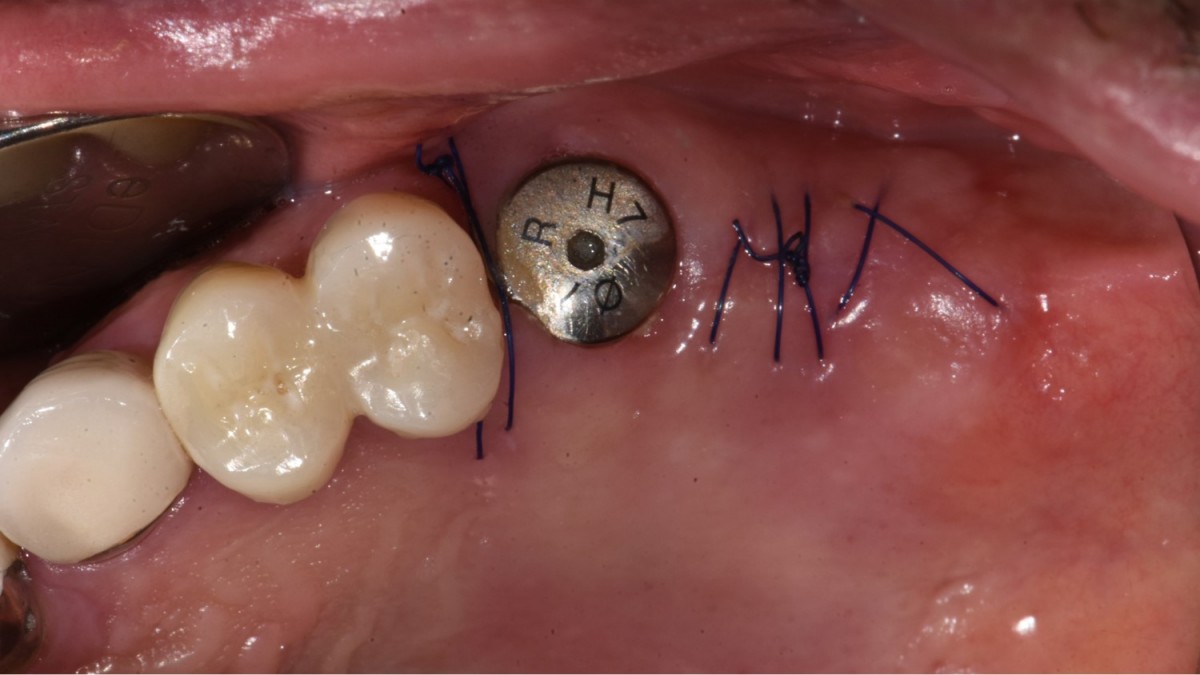

▲2 implants were placed. ArumDentistry NB1 5*10 (30Ncm) in the 1st molar and 5*10 (10Ncm) in the 2nd molar.

▲HA was inserted into the membrane with a hole in the middle and then inserted into the place where the Direction Pin was pulled out